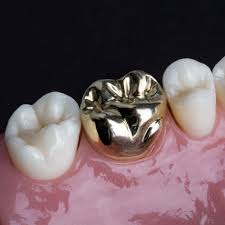

| 골드 크라운 | 50~55만 원 |